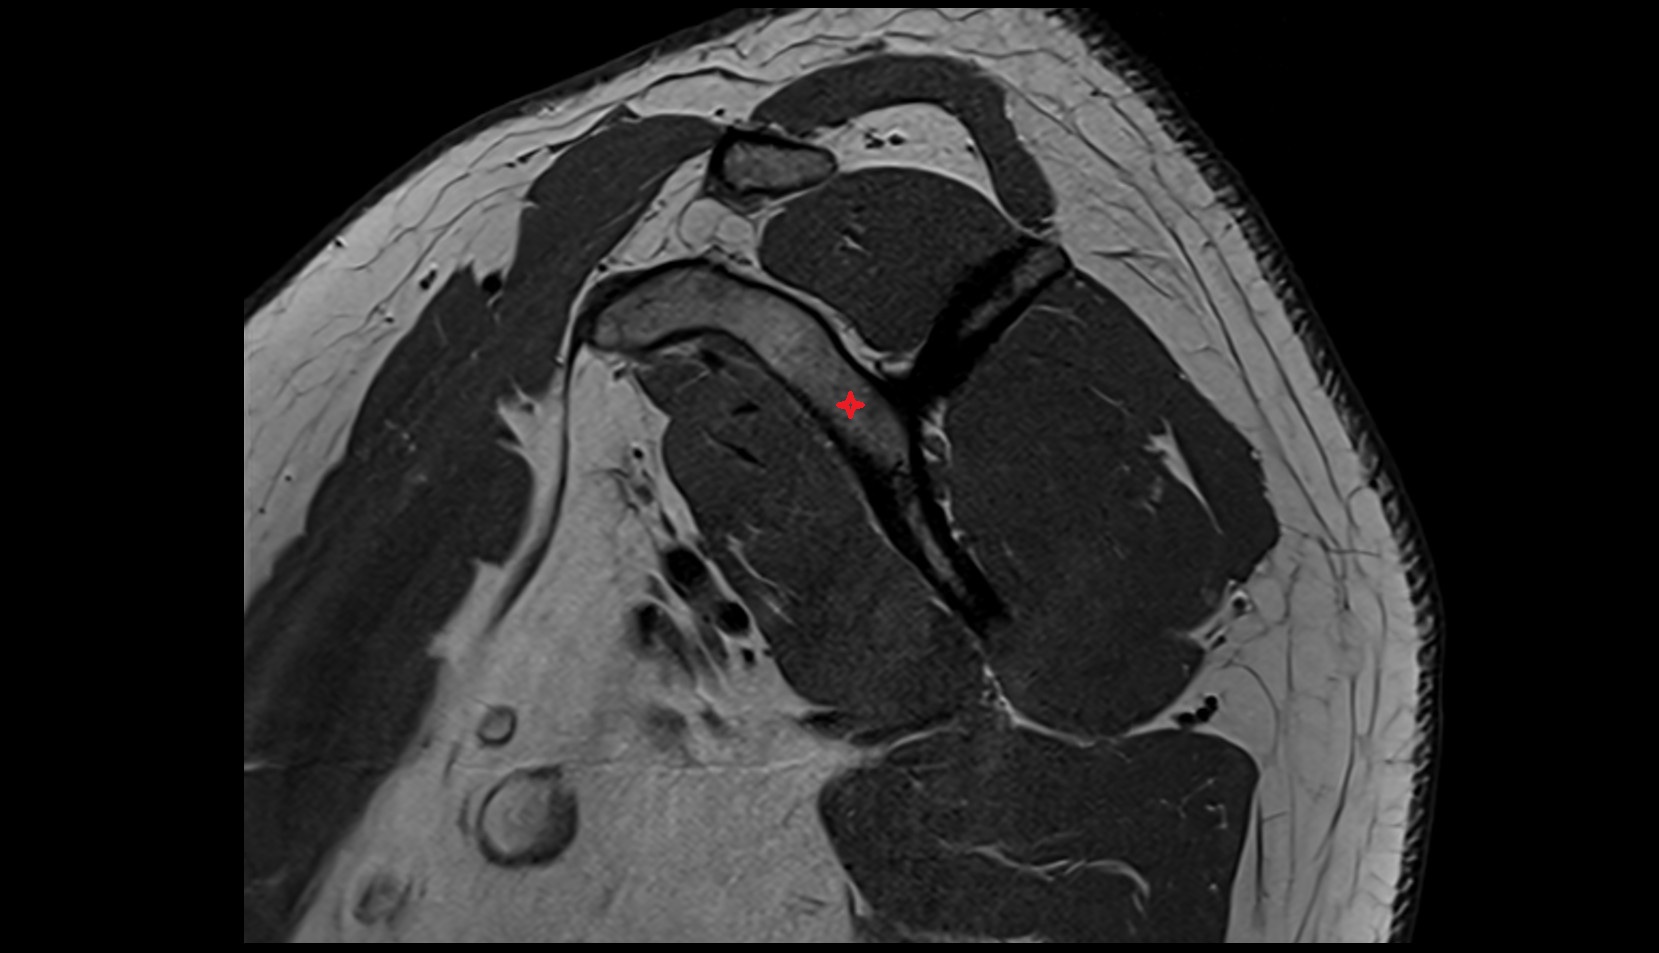

- Shoulder joint (glenohumeral joint)

- Glenoid labrum

- Supraspinatus tendon

- Infraspinatus tendon

- Subscapularis tendon

- Glenohumeral joint capsule